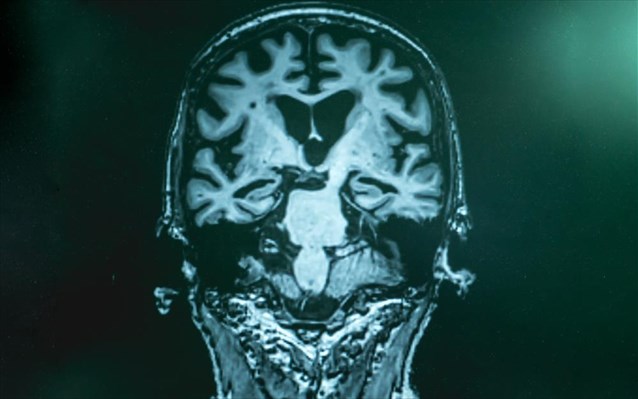

Ένα γονίδιο που σχετίζεται με τη νόσο του Alzheimer μπορεί να επηρεάσει τον εγκέφαλο, ιδιαίτερα τη γνωστική υγεία, ακόμη και πριν από την ενηλικίωση, σύμφωνα με τα ευρήματα μίας νέας μελέτης.

Μια ομάδα ερευνητών στο Πανεπιστήμιο της Καλιφόρνιας, Riverside, διαπίστωσε ότι η γνωστική υποβάθμιση της υγείας αρχίζει νωρίτερα σε άτομα που πάσχουν από νόσο του Alzheimer.